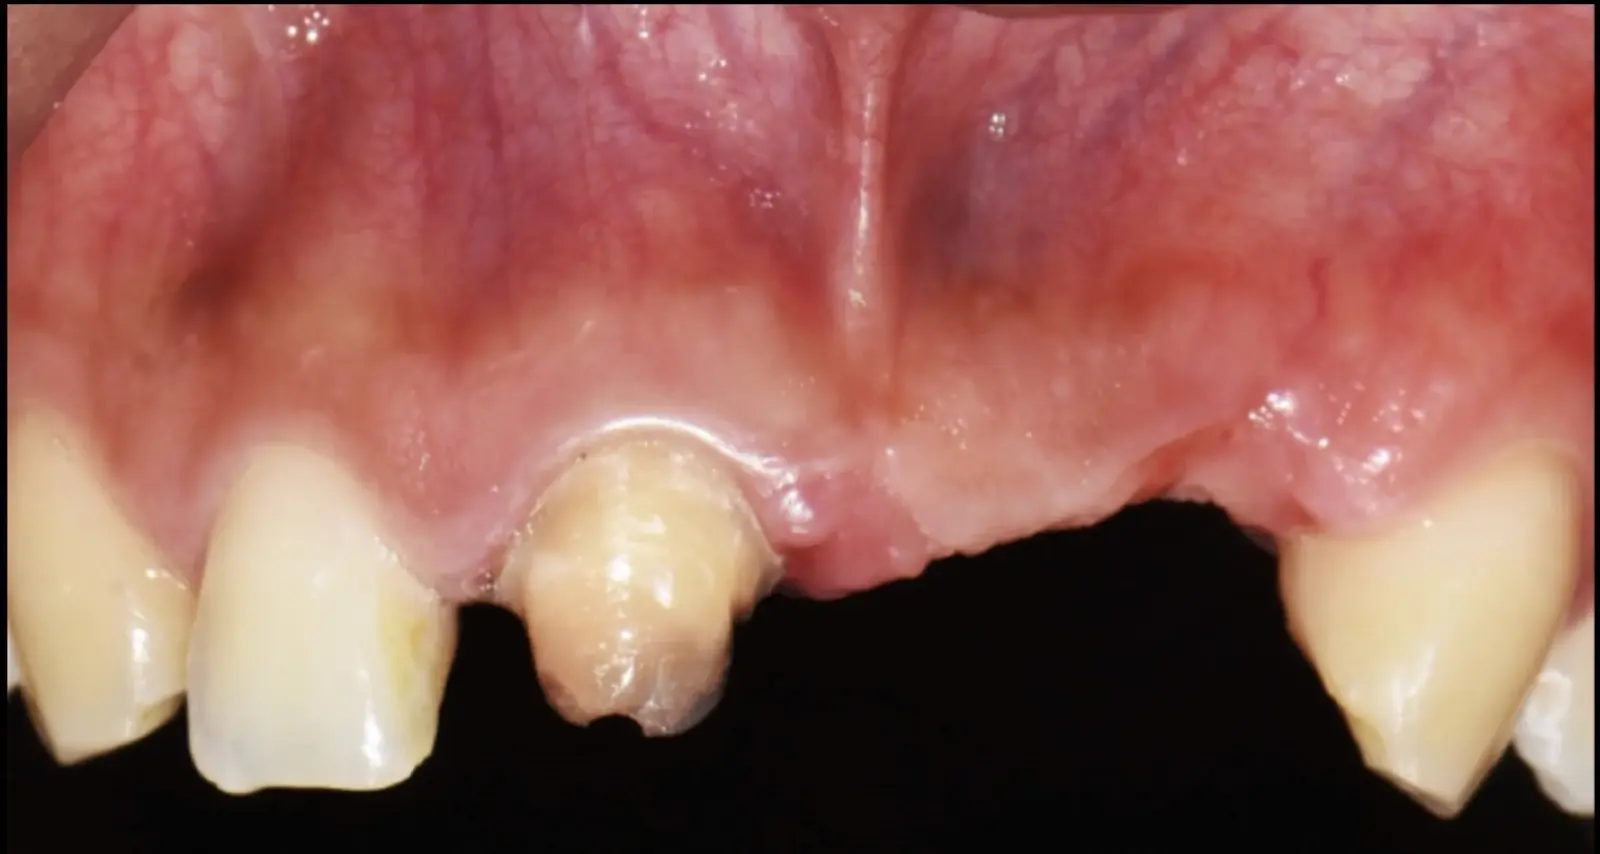

Figura 35. Decolado a espesor total sobrepasando la línea mucogingival (a, b).

Figura 36. Defecto óseo y severa reabsorción ósea horizontal: vista clínica (a) y corte tomográfico (b).